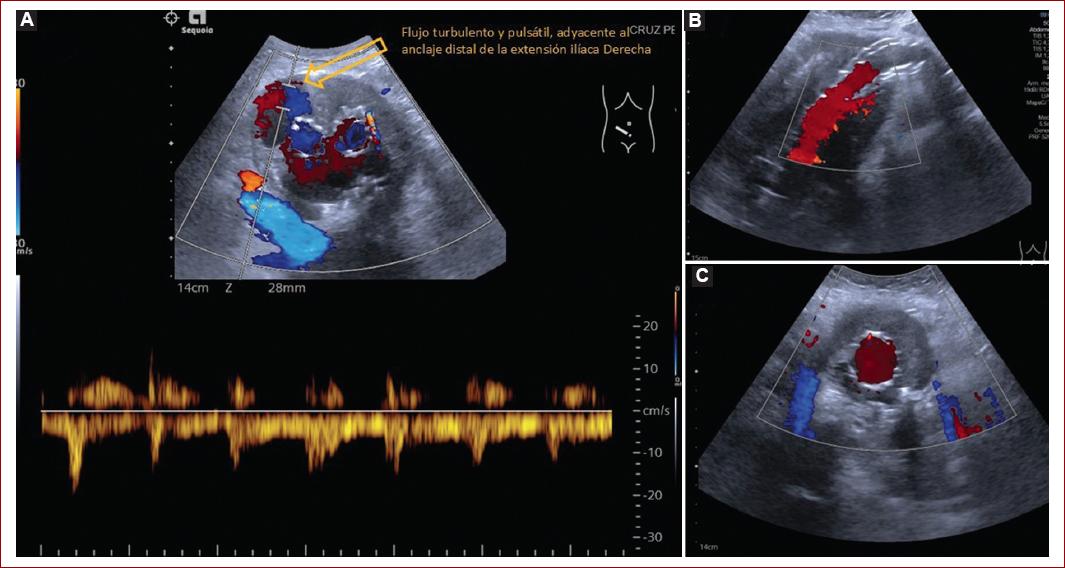

Análisis en Doppler color y espectral

- Análisis en color y espectral de la totalidad de la endoprótesis y sus extensiones que demuestre su permeabilidad.

- Búsqueda de flujo turbulento en tortuosidades y/o acodamiento en ramas y extensiones ilíacas.

- Evaluación de los sitios de fijación proximal y distal para identificar la presencia de flujo por fuera de la luz de la endoprótesis, así como de sus extensiones.

- Evaluar la permeabilidad y flujo de las arterias renales, mesentérica superior y tronco celíaco.

- Evaluar la permeabilidad de las ramas arteriales del saco aneurismático (arterias lumbares, arteria mesentérica inferior), así como la dirección del flujo de cada una de las ramas (Fig. 4).